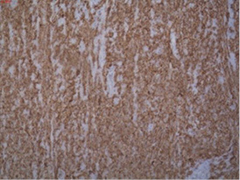

A 46-years-old female patient presented to the emergency department with clinical signs of intestinal obstruction. The patient reported cramp and abdominal pain, and absence of flatus and stool passage one day prior to the exam. She had no previous abdominal surgery nor visible groin herniation on physical examination. The serum analysis showed C-reactive protein value of 5.80 (0.0–5.0 mg/L) and serum Iron level of 5.80 (6.6–28.3 μmol/L). Plain abdominal upright X-ray image confirmed the suspicion for intestinal obstruction (Figure 1).

Figure 1. Plain abdominal X-ray with small bowel air-liquid levels